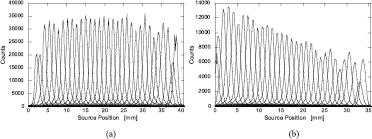

To evaluate the intrinsic spatial resolution of the DOI detector module, coincidence response functions (CRFs) of the detector pair located at a 40 mm distance were measured. This was done by scanning a 0.25 mm diameter 22Na point source of approximately 0.7 MBq along the central line between them, at γ-ray incident angles of 0° and 22.5° to the crystal surface, in 0.12 and 0.185 mm scan steps, respectively. Each angle corresponds to the center and half positions of the transaxial FOV in the system ring configuration. The intrinsic spatial resolution measurement setup is shown in figure 4. The single-event data of the detector pair at each step position were sent to the data acquisition servers and stored in a hard disk. The acquiring times for each position were 20 and 10 min for 0° and 22.5°, respectively. After the measurements, coincidence detections were performed off-line by software and the coincidence counts were plotted as a function of the source position for each layer combination. The intrinsic spatial resolutions of the detector pair were derived from the FWHM values of the CRFs, by fitting a Gaussian function.

The CRFs of the center unit pair of five units in the first layer, for both 0° and 22.5°, are shown in figure 5. The averaged FWHM values in the first layer pair (layer 0–0) were 1.08 mm and 1.25 mm for 0° and 22.5°, respectively. The FWHM values in the edge region of a crystal block tend to be worse than those in the central region, especially at 22.5°. This appears to be due to the Anger logic calculation used to identify crystal segments in a crystal block. With deeper layer pairs, the FWHM values became degraded, due to the longer crystal sizes and lower coincidence counts. The averaged FWHM values with their standard deviations (SDs) for the CRFs for each layer combination are summarized in table 2.

Figure 5. Coincidence response functions (CRFs) of the center unit pair of five units in the first layer, for (a) 0° and (b) 22.5°.